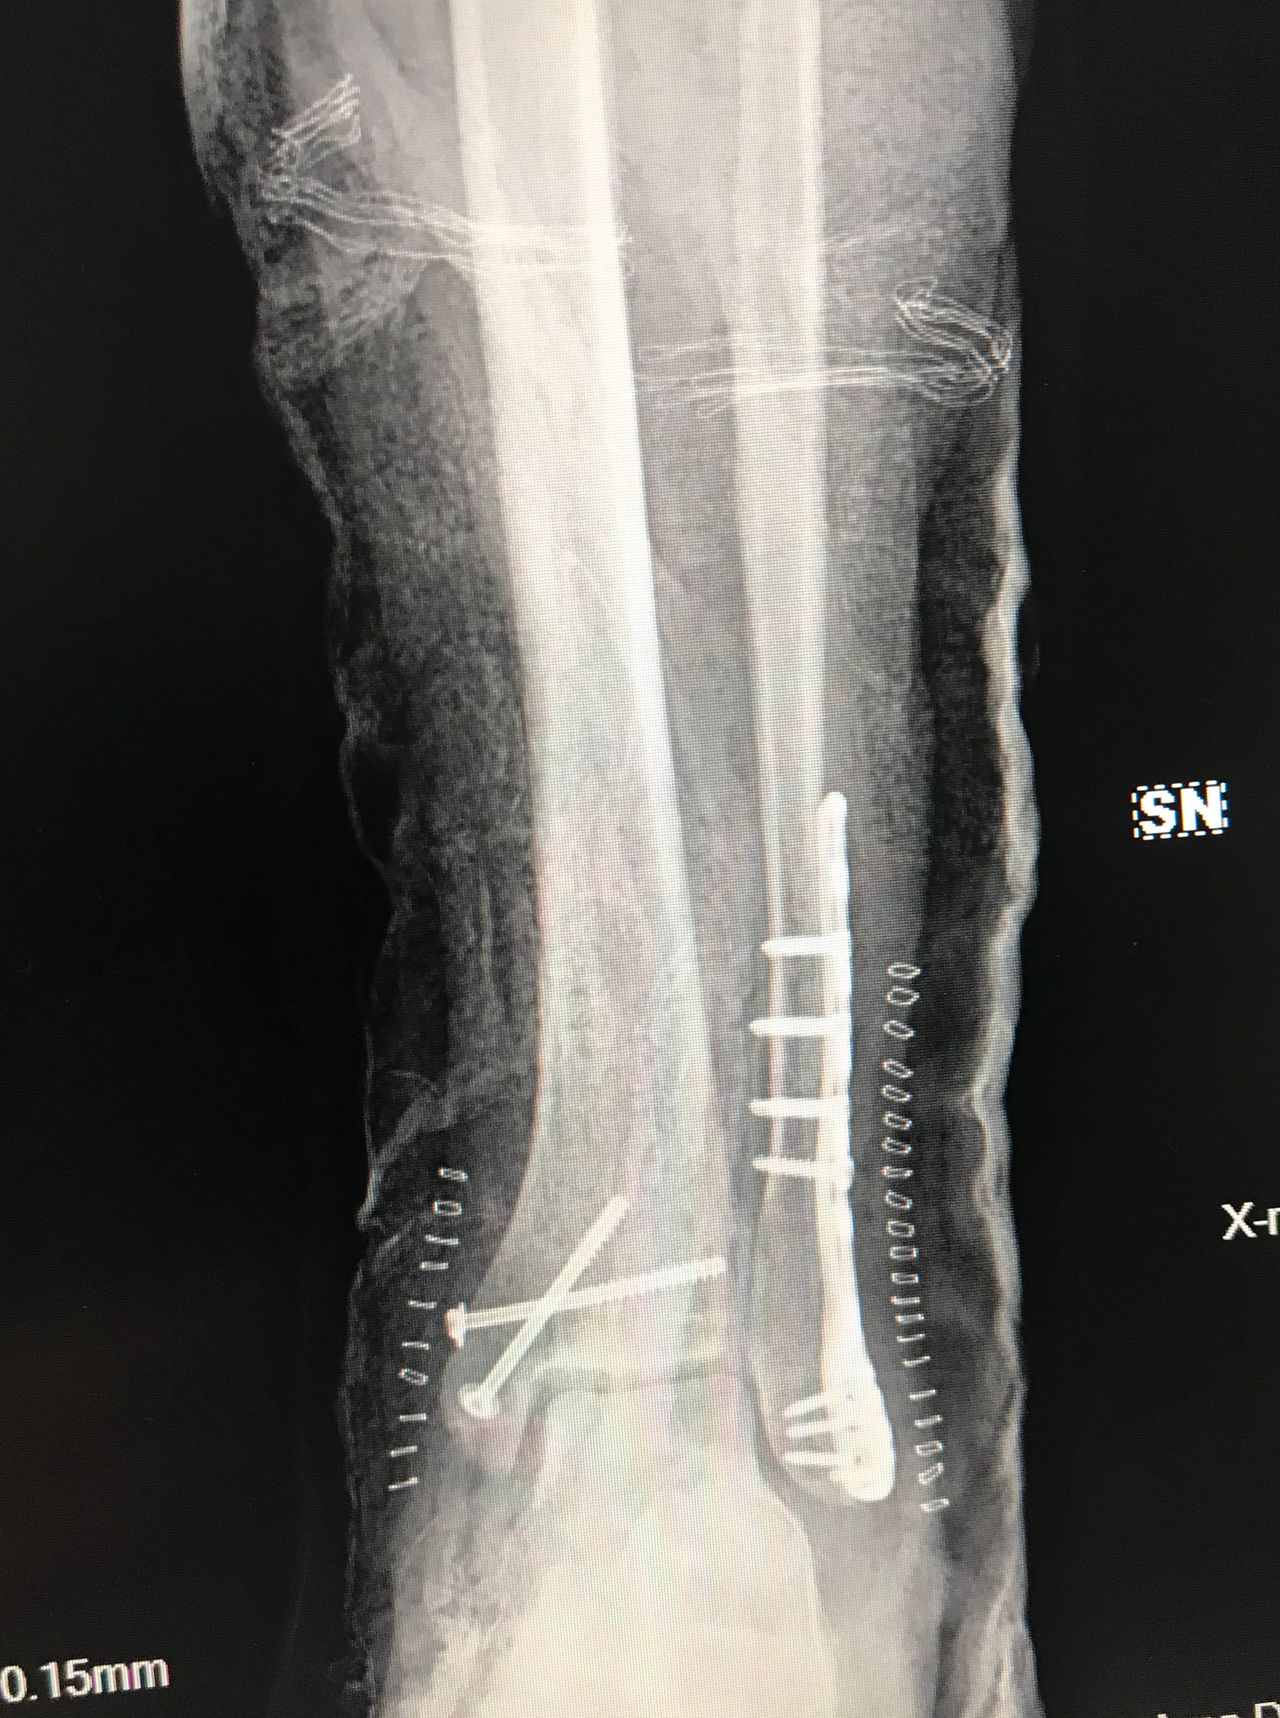

Traumatologia

• Ortopedia e traumatologia del sistema motorio